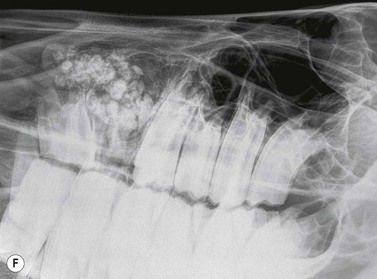

image image image image image image

Fig. 13.41 Radiographic signs of periapical infection. (A) Radiolucent halos are evident around both roots of an infected 408, with widening of periodontal space, sclerosis of the ventral mandibular cortex and periosteal new bone deposition. (B) A zone of sclerosis is present around this infected 306. The affected apex is somewhat blunter than those of adjacent teeth; however, this can be a normal feature of 06s. An arrow points to a small radio-opaque marker placed on the skin at the site of facial swelling. (C) Infected 108. A periapical radiolucent halo surrounded by marked sclerosis is evident around the infected apex of this tooth, which lies outwith the rostral maxillary sinus in this horse. (D) Gross destruction of the architecture of this infected 407 dental bud is present, with loss of much of the apical aspect of its crown. Multiple radio-opaque fragments are present in the alveolus, which may represent dental fragments or cementoma formation. A draining tract (with probe inserted) and gross mandibular new bone formation are evident. (E) Marked sclerosis is present around an apically infected 210. This horse had concurrent sinusitis. (F) Massive reactive cementoma deposition is present around the apex of chronically infected 207. Dystrophic calcification of the nasal conchae is likely also contributing to the radio-opaque appearance in the area rostral to the alveolus of 207. Most of the reserve crown of this tooth was still present; however, it is quite radiolucent, due to demineralization caused by chronic infection.